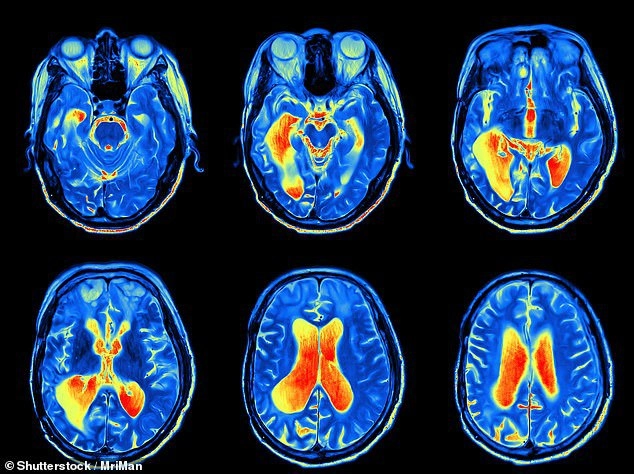

В исследовании использовался МРТ-сканер для анализа мозга одиннадцати взрослых, которые регулярно играли в эту игру в детстве, и записывал итоговую активность, когда испытуемым показывали изображения покемонов.

Мало того, что мозг людей, которые играли в покемонов в детстве, более заметно реагировал на изображения вымышленных существ, но все записанные действия происходили в одной и той же области мозга — в складке, расположенной сразу за ухом, которая называется затылочно-височной бороздкой.